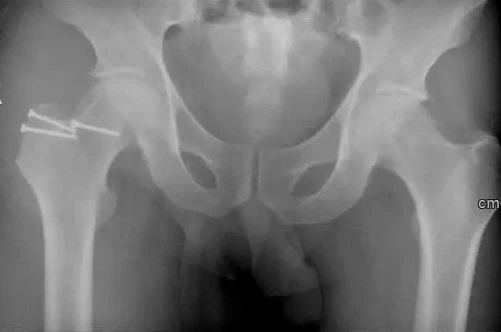

术前X光片